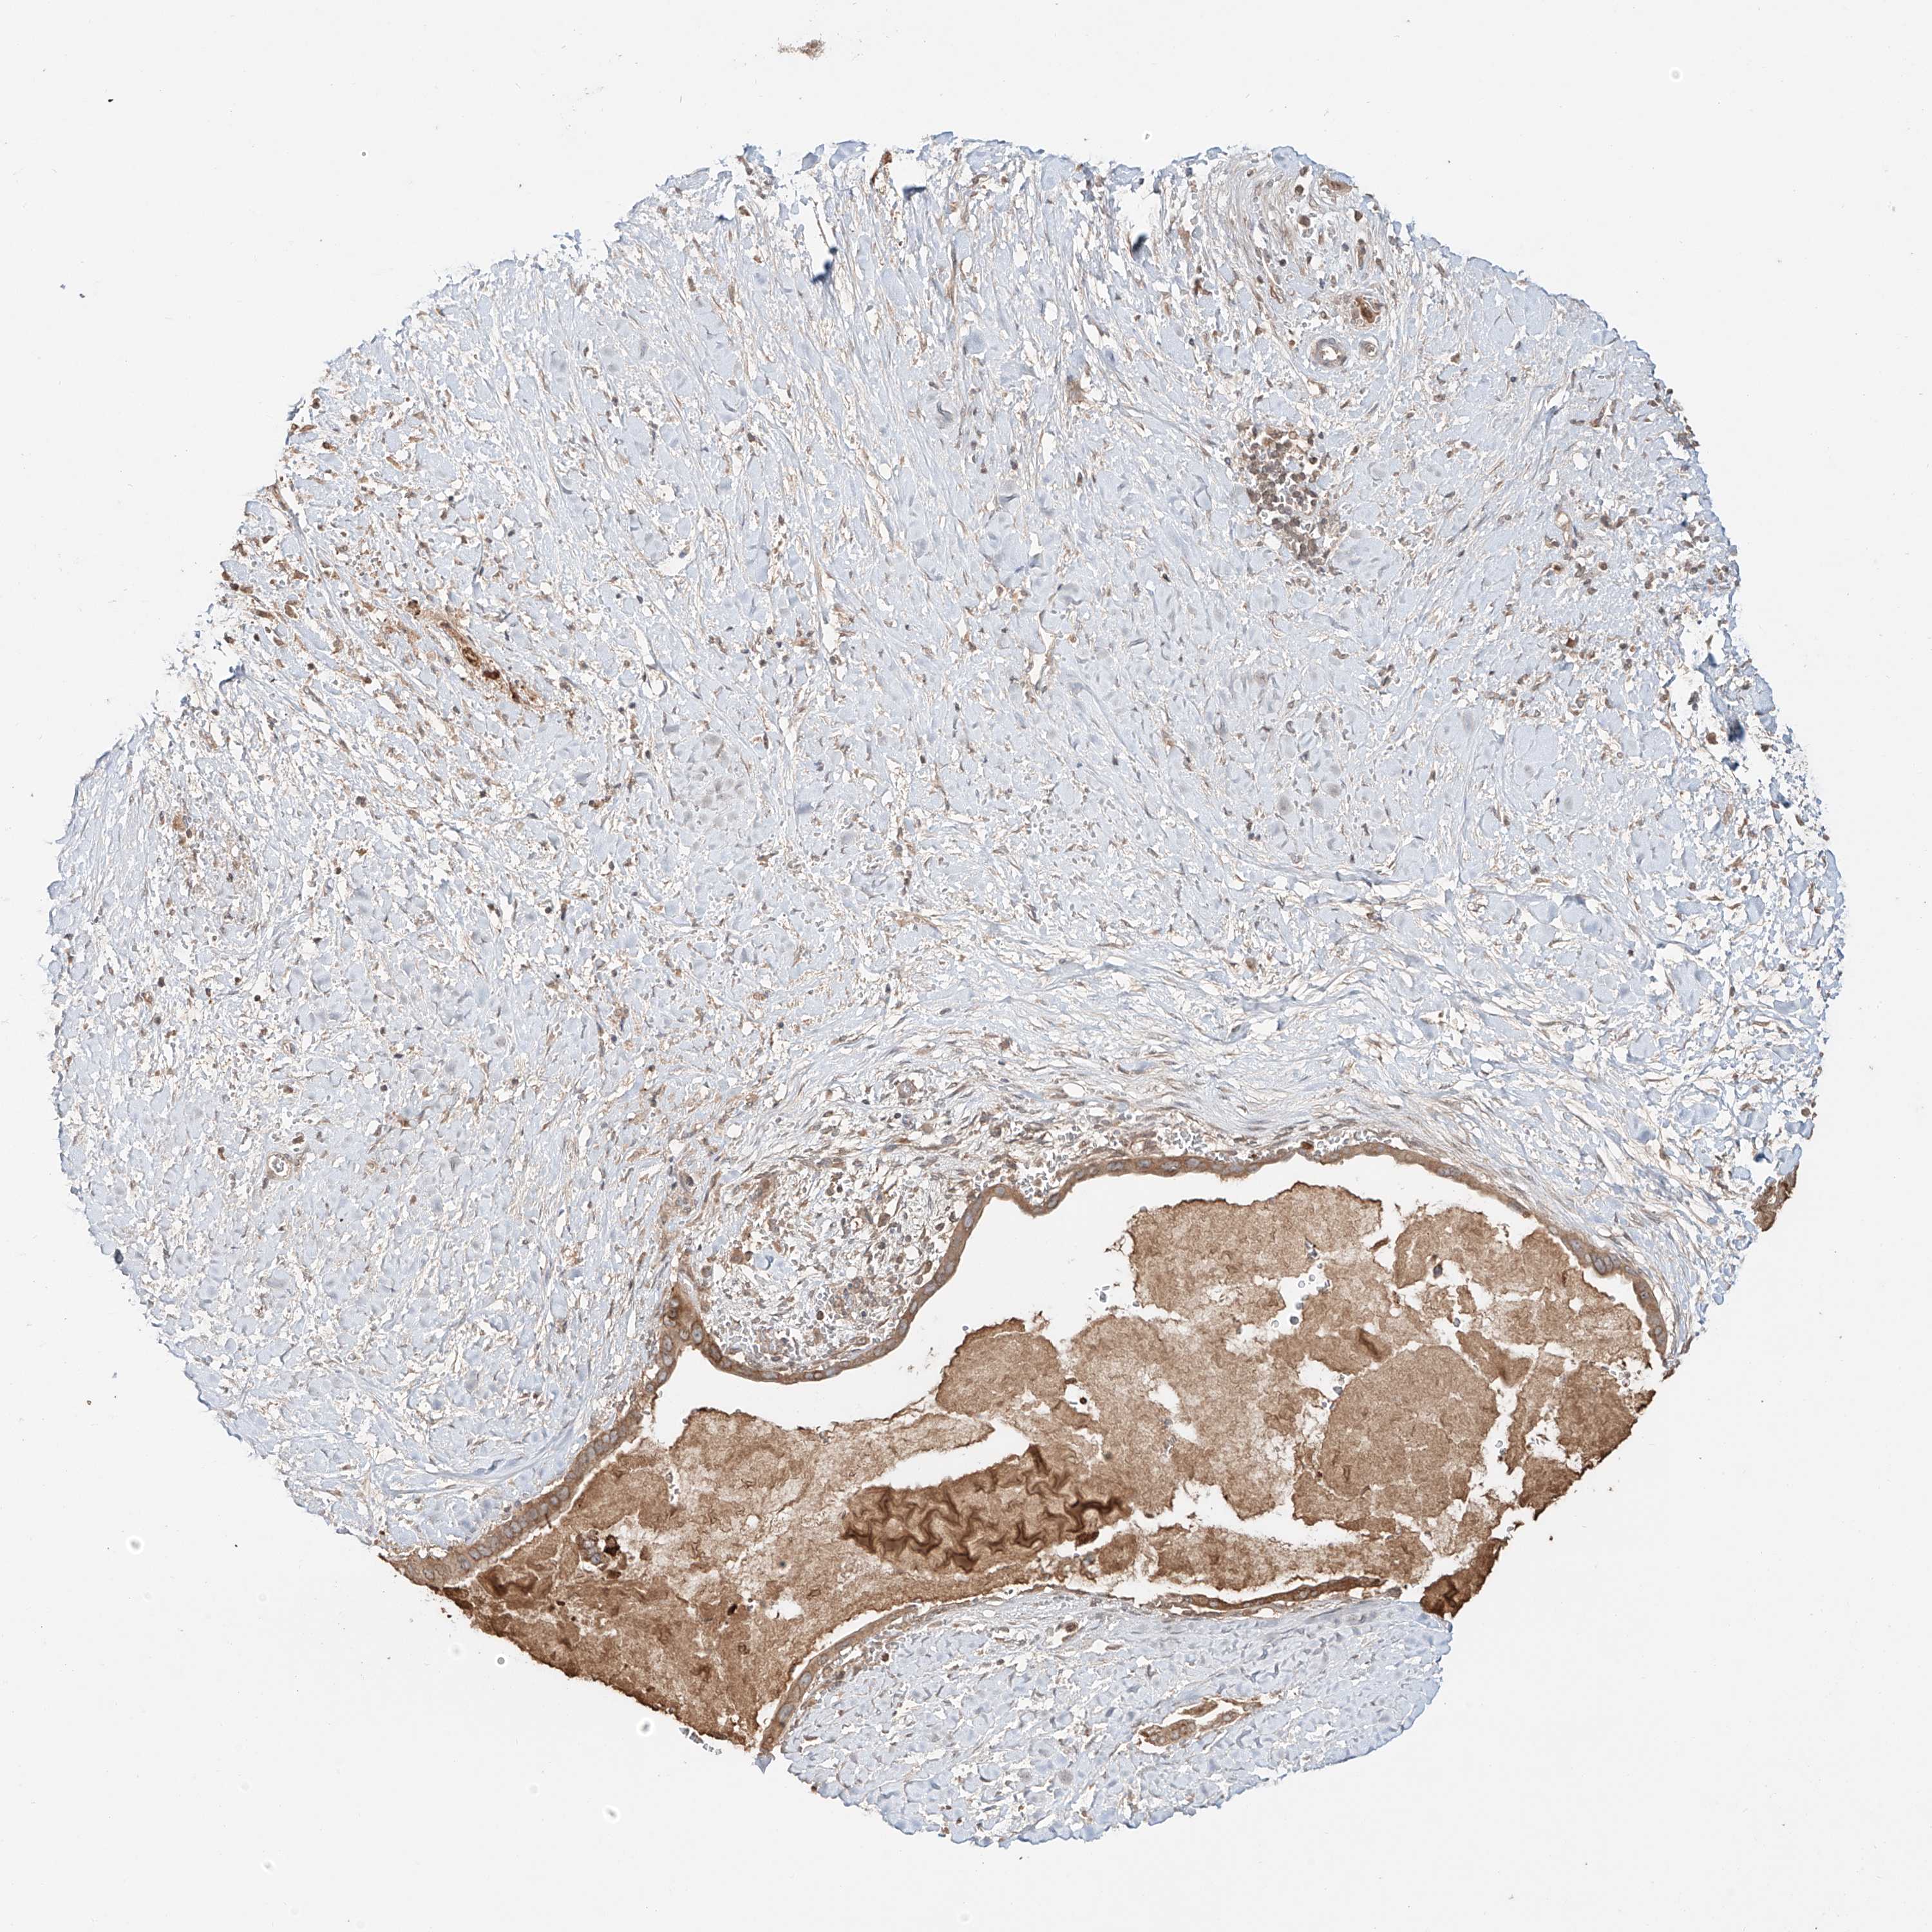

PANCREATIC CANCER - Protein expressioni

A mouse-over function shows sample information and annotation data. Click on an image to view it in a full screen mode. Samples can be filtered based on level of antibody staining by selecting one or several of the following categories: high, medium, low and not detected. The assay and annotation is described here.

Note that samples used for immunohistochemistry by the Human Protein Atlas do not correspond to samples in the TCGA dataset.

Antibody stainingi

Antibody staining in the annotated cell types in the current human tissue is reported as not detected, low, medium, or high, based on conventional immunohistochemistry profiling in selected tissues. This score is based on the combination of the staining intensity and fraction of stained cells.

Each image is clickable and will lead to virtual microscopy that enables deeper exploration of all samples and also displays staining intensity scores, fraction scores and subcellular localization as well as patient and tissue information for each sample.

Antibody HPA026653

Antibody HPA030053

Antibody CAB034294

Adenocarcinoma, NOS